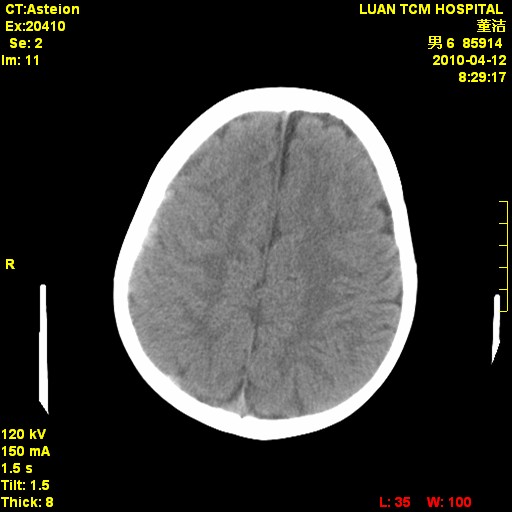

标题: PED3404:有结果,先猜猜这是啥病表现?男,12岁。 [打印本页]

标题: PED3404:有结果,先猜猜这是啥病表现?男,12岁。

无病史无骨窗,12岁可以可考虑白血病等。

鉴别:骨肉瘤、ewing's瘤、骨淋巴瘤、板障型脑膜瘤、嗜酸性肉芽肿等

右侧额顶部自颅板向内近似半圆高密度影,周围无明显水肿,考虑:脑外血肿?脑膜瘤?淋巴瘤?